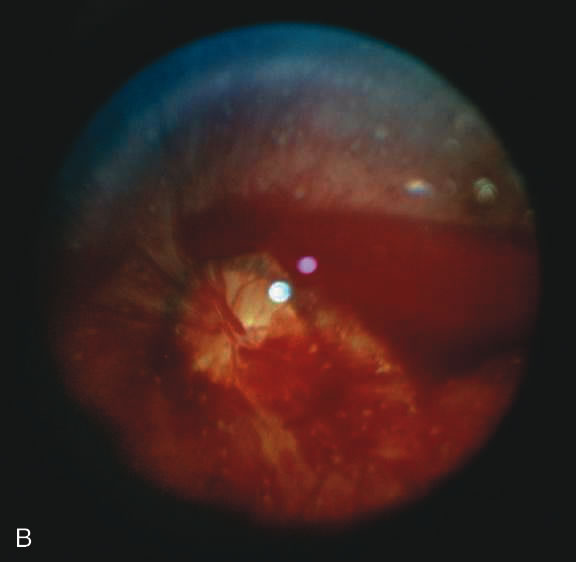

Findings range from a normal fundus to a small number of scattered intraretinal hemorrhages in the posterior pole to massive, confluent hemorrhages from the posterior pole to the ora serrata.(Fig. 10) The hemorrhages may be subretinal, deep intraretinal (dot/blot), nerve fiber layer (flame shaped) or preretinal.19,45 Intraretinal hemorrhages are more common than preretinal or subretinal hemorrhages.32,46 Preretinal hemorrhages must be distinguished from traumatic retinoschisis (see later), which has particular diagnostic significance. White-centered retinal hemorrhages, although classically associated with endocarditis, can occur in any condition that causes retinal hemorrhages, including SBS. Vitreous hemorrhage may be small to massive, and may occur secondary to escape of blood from intraretinal collections or from torn vessels.19 Although vitreous hemorrhage may occur at the time of injury, it may also be a delayed finding occurring 1 to 3 days or more after the initial trauma.47,48

Fig. 10. Retinal hemorrhages in SBS may range from a nonspecific mild posterior pole distribution (10A) to a more characteristic picture of too numerous to count, multiple, extensive intraretinal hemorrhages (in this many with white centers) with subhyaloid hemorrhage (10B, 10C)

The pathophysiologic mechanisms of retinal hemorrhage in SBS are varied. Vitreous and perhaps orbital shaking is likely to be involved in most of the vitreoretinal injuries. In children, the vitreous is well attached to the retina at the macula, blood vessels, and the periphery. Shaking of an infant causes the vitreous to shake, which, in turn, applies shearing forces to the retina at points of firm attachment. These shearing forces at the macula may split the retina at any layer, causing the formation of a cystic cavity, which may be filled partially or completely with blood (Fig. 11). This traumatic retinoschisis has been well documented in abuse cases by ultrasound, electroretinogram, and pathology.34,58,60,61,62,63,64 Histopathology reveals a widening of the retinal layers or a stripping of the internal limiting membrane. The vitreous may stay adherent or detach. Clinically, to recognize this important finding in SBS, the examiner may observe a hemorrhagic or hypopigmented curvilinear edge to the schisis cavity, with or without a fold in the retina (Figure 11).50,65,66 Recognition of this edge helps distinguish retinoschisis from subhyaloid hemorrhage. However, subhyaloid hemorrhage, which may have originated from blood breaking out of a schisis cavity, may obscure the underlying schisis. It is important to follow any potentially shaken child with preretinal blood in the macula until that blood has cleared as the signs of schisis may be unmasked as the blood resorbs thus confirming the diagnosis of SBS. The retinal fold or hypopigmented line may be a complete circle or just an arc. In the long term, these patients may have surprisingly few sequelae and good vision as the cavity flattens spontaneously. There may also be findings of permanent curvilinear, hypopigmented scars or retinal folds. These provide clues to prior abuse.67

Fig. 11. Putscher retinopathy in SBS. Note circumlinear demarcation of macular retinoschisis containing small layer of blood.

There remain still other theories for retinal hemorrhage in SBS that also seem to play a minor role. Some have suggested a Purtscher-like mechanism due to an increase in intrathoracic pressure when the perpetrator squeezes the child's chest. Although the characteristic white retinal patches of Purtscher retinopathy may be seen in SBS (Fig. 11), there appears to be no correlation with rib fractures,35 and the finding is very uncommon. The failure to see significant retinal hemorrhaging after the chest compressions of cardiopulmonary resuscitation in both animal models and humans also argues against a Purtscher-like mechanism.